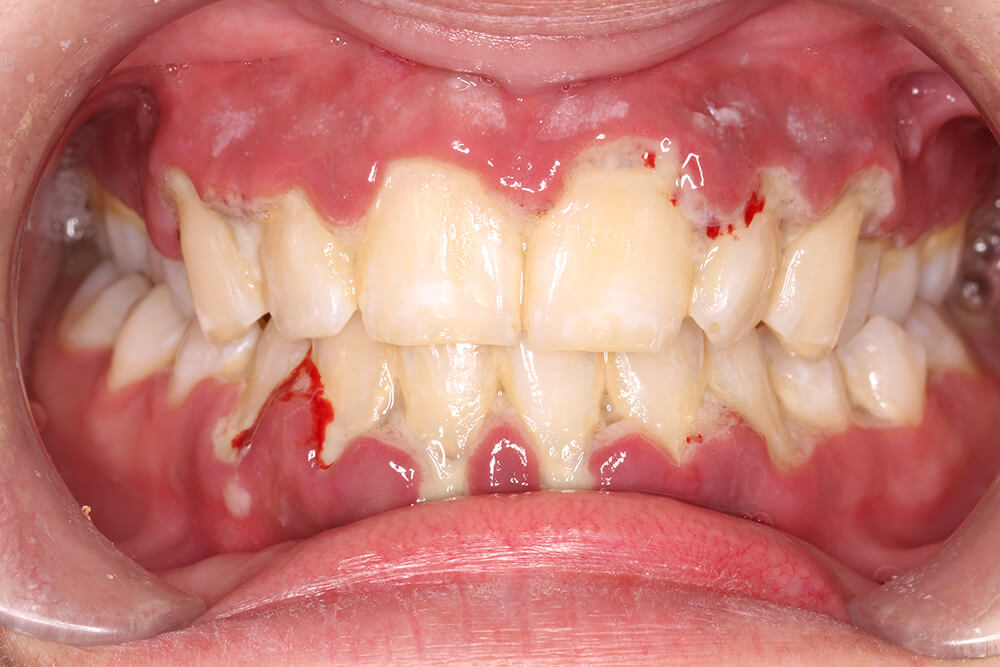

Periodontal diseases as a whole actually include different grades and stages, reflective of a progressive deterioration of the supporting structures of the teeth. In advanced stages, these pathologies can lead to tooth loosening, mobility, and ultimately tooth loss [31, 32]. The classification of periodontal diseases has evolved significantly [33], with recent revisions taking into account the intricate relationships between oral health disturbances and associated systemic conditions [34]. This paradigm shift recognises the periodontal tissues as a mirror of overall patient health [35]. It has been known for nearly 30 years that certain aggressive periodontal conditions, such as necrotising ulcerative gingivitis or periodontitis (Fig. 5), may serve as indicators of underlying severe systemic disorders [36]. These conditions can be early manifestations of serious health issues like leukaemia or acquired immunodeficiency syndrome (AIDS), underscoring the importance of comprehensive health assessment in dental practice [37]. This evolving perspective on periodontal health emphasises the need for interdisciplinary approaches in healthcare. Dental professionals must be vigilant not only while treating local oral conditions but also in recognising potential systemic implications. Conversely, medical practitioners should be aware of the oral manifestations of systemic diseases. Thus, when patient care involves serious pathologies, it is beneficial to coordinate practitioners from all the involved specialities within the same structure, hospital for example [38].

Fig. 5.

Ulcero-necrotic gingivitis in a 30-year-old woman. The gum line is necrotic and the interdental papillae are severely destroyed.